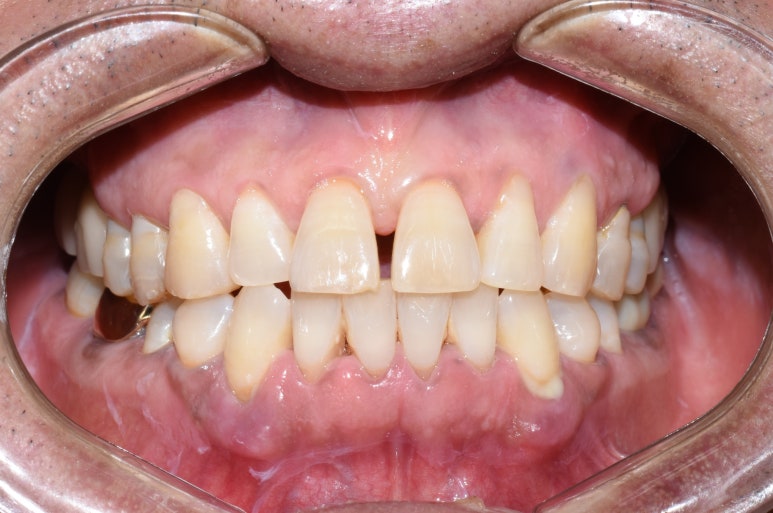

↑치료 전 사진입니다. 큰 어금니 쪽에 치아들이 성하지 않아

씹기가 힘든 상태입니다.

↑치료후에는 큰 어금니쪽 치아들을 윗니어금니 임플란트, 아랫니는 크라운 등으로 회복시켜

양쪽으로 잘 씹을 수 있게 되었습니다.